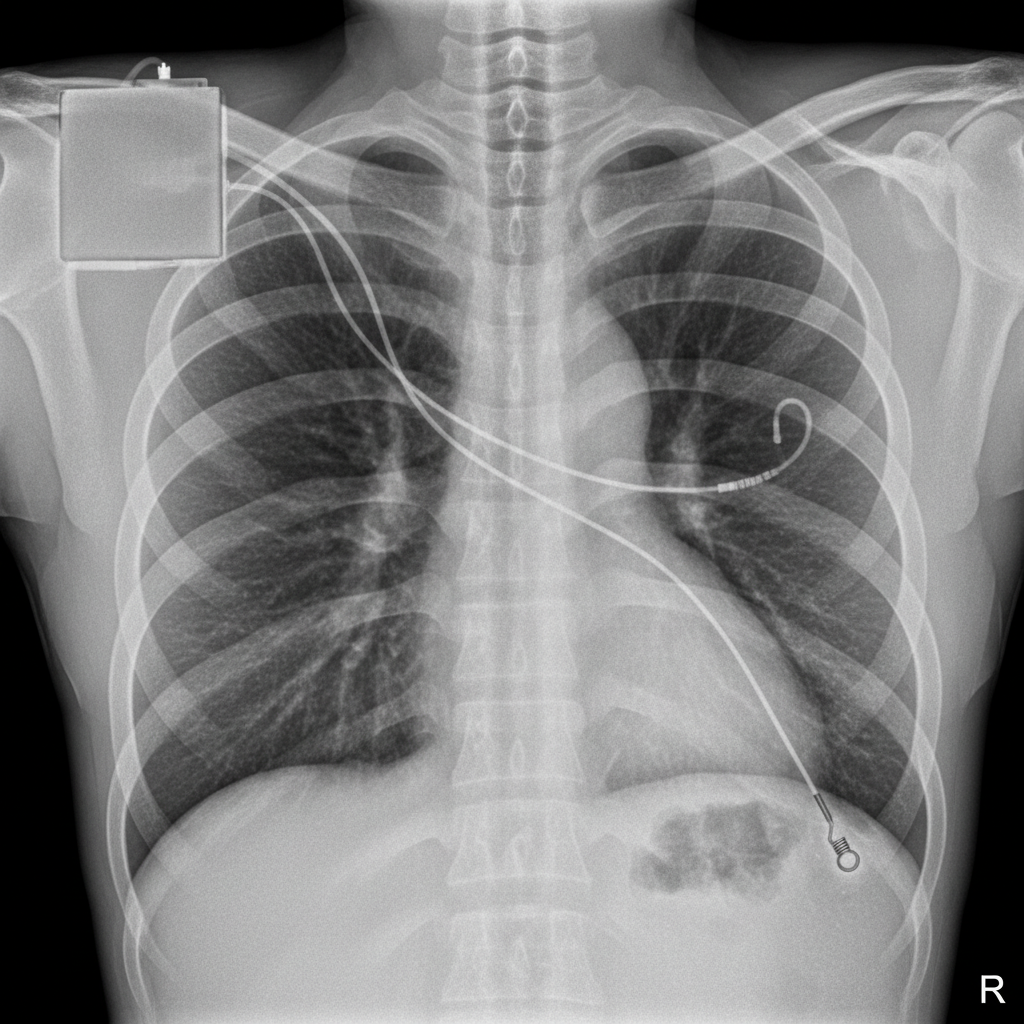

What is the location of the atrial and ventricular pacemaker lead tips, respectively?

Explanation: ***Right atrium and extracardiac*** - The **atrial lead** is correctly positioned in the **right atrial appendage**, which is the standard placement for dual-chamber pacemakers. - The **ventricular lead** has perforated through the myocardium and is positioned **extracardiac**, indicating a serious complication requiring immediate attention. *Right atrium and right ventricle* - While the atrial lead is correctly positioned in the **right atrium**, this option incorrectly describes normal ventricular lead placement. - In this case, the ventricular lead has **perforated** beyond the right ventricle into an extracardiac position. *Extracardiac and right ventricle* - The **atrial lead** is actually properly positioned within the **right atrium**, not extracardiac. - This option incorrectly describes the ventricular lead as being in the right ventricle when it has actually **migrated extracardiac**. *Both leads are extracardiac* - The **atrial lead** remains properly positioned in the **right atrial appendage** and has not perforated. - Only the **ventricular lead** has perforated, making this description of both leads being extracardiac incorrect.